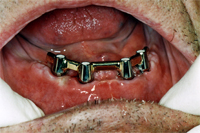

Am 2. Oktober 2006 wurden unter Aufklappung vier Implantate gesetzt. Eine Woche später kommt der Patient zur Nahtentfernung (Abb. 1). Die postoperative Schwellung ist verschwunden und die Nähte werden entfernt. Die Einheilkappen sind für die Abdrucknahme vom Implantat entfernt (Abb. 2). Mit der bestehenden Prothese wird nun der Abdruck genommen. Noch gleichentags fertigt der Techniker den Implantatsteg an, den ich im Mund provisorisch festschraube (Abb. 3).